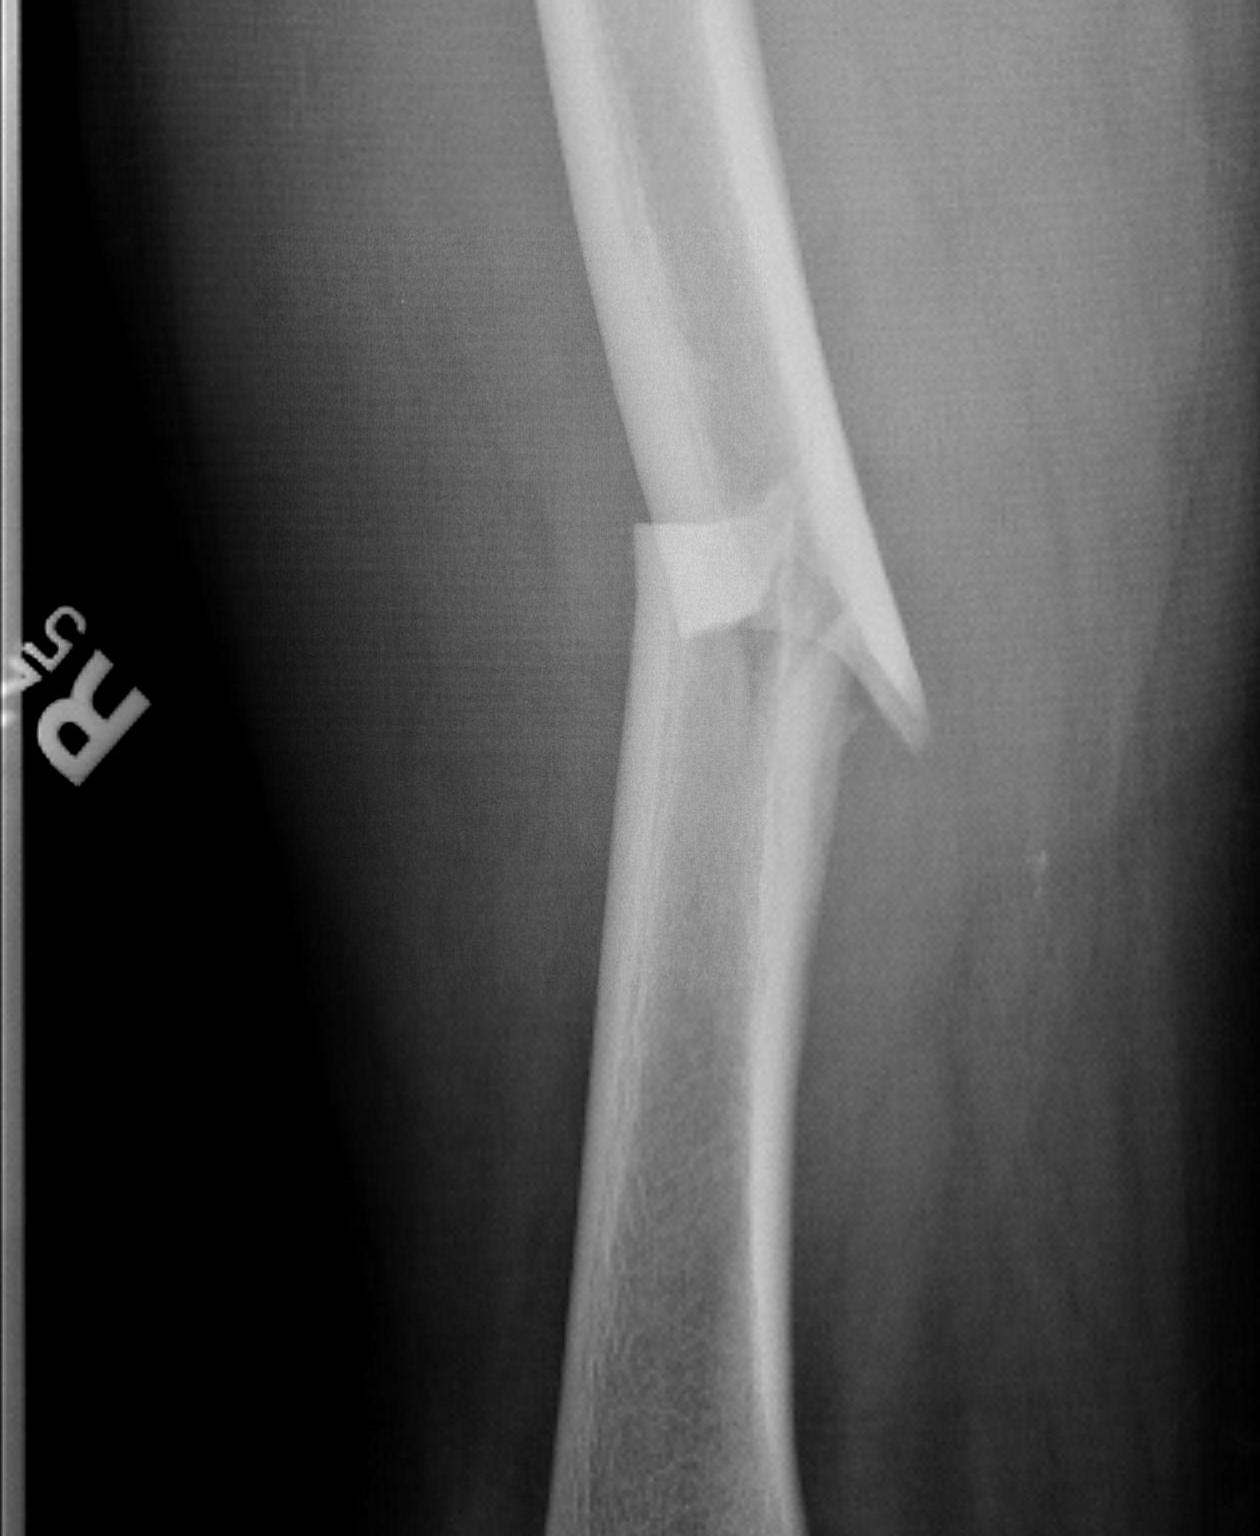

Winquist Classification

Type 1

- minimal or no comminution

Type 2

- < 50% comminution

Type 3

- 50 - 100% comminution

- inherently unstable

- needs distal locking

Type 4

- segmental comminution

- no contact or inherent stability